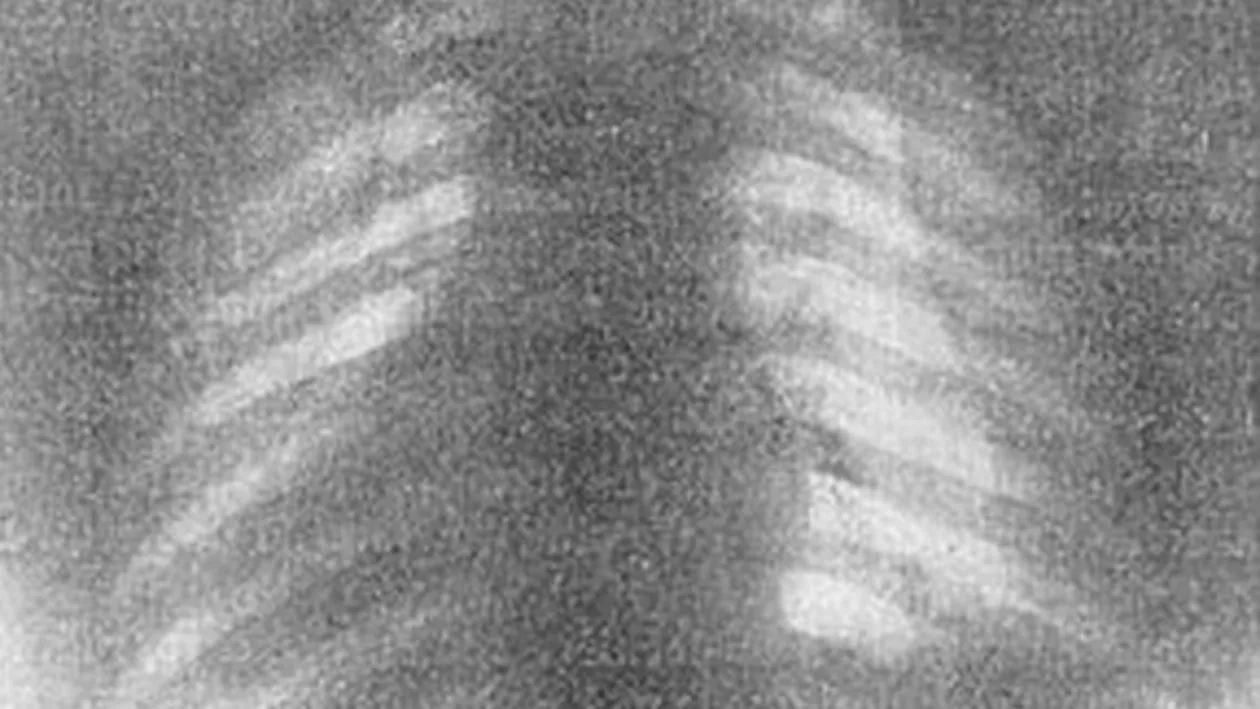

In radiografiile „normale” se pot vedea coaste paralele si organe pozitionate corect. In cele facute unor femei care au purtat corsete, descoperim coaste indoite si organe pur si simplu strivite.

„Corsetele comprima continutul torsului, in special inima si plamanii”, a explicat medicul Natalie Azar.